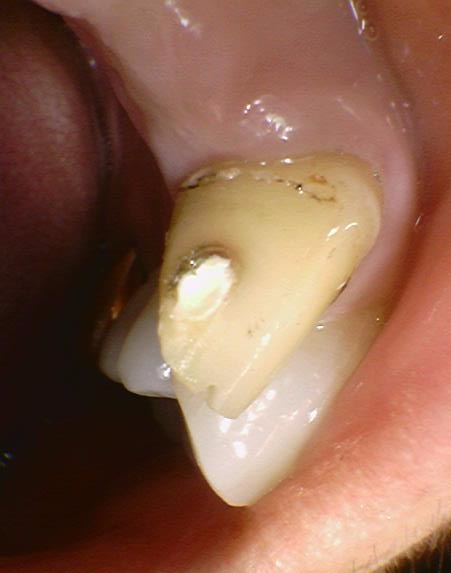

브릿지 깨진 부위 '임시로' 떼워드렸습니다.

환자분과 상담후, 오래된 브릿지고 몇 십년전 잇몸에 맞춘 상태였기 때문에 잇몸이 내려가면서 브릿지에 싸여있어야 할 치아도 노출 되어 있었기 때문에 브릿지를 새로 제작하기로 하였습니다.

일단 앞니라서 신경쓰인다고 하셔서 브릿지 깨진 부위를 임시로 간단히 떼워드렸구요

며칠 간만 쓸, 빠르게 임시로 떼운 거라서

이쁘진 않습니다~

그 후 며칠 후에 오셔서 브릿지를 뜯어냈는데요,(시간이 되시면 당일에도 가능합니다)

치아가 많이 상해있진 않지만 조금 더 다듬어야 했습니다.

몇 십년전 잇몸에 맞춘 상태였기 때문에 잇몸이 내려가면서 브릿지에 싸여있어야 할 치아도 노출 되어 있었구요.